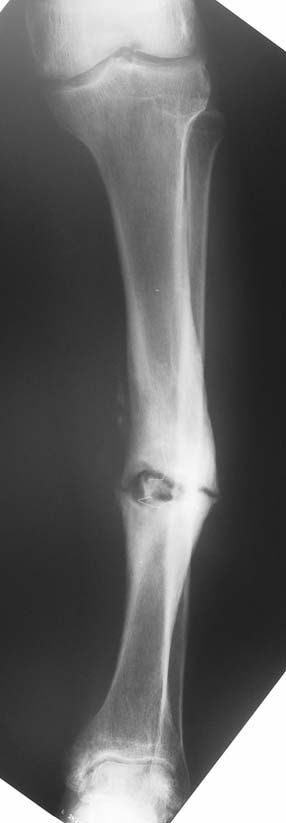

Chronic osteomyelitis leads to necrosis of bone and soft tissues. Dead bone is a nidus which hosts pathogenous microorganisms. Defence mechanisms of the host is usually not in optimum condition to deal with microorganisms. Antibiotics can’t reach the infection site because blood flow is disrupted. For these reasons, dead bone has to be completely removed by radical debridement.

Appropriate radical debridement necessitates excision of all necrotic bone and soft tissues, and frequently causes instability at the involved extremity. The remaining bone and soft tissue defect has to be fixed and reconstructed. The distraction osteogenesis method of Ilizarov is used successfully for achievement of union, correction of the deformity, elimination of limb length inequality and reconstruction of segmental bone defects.